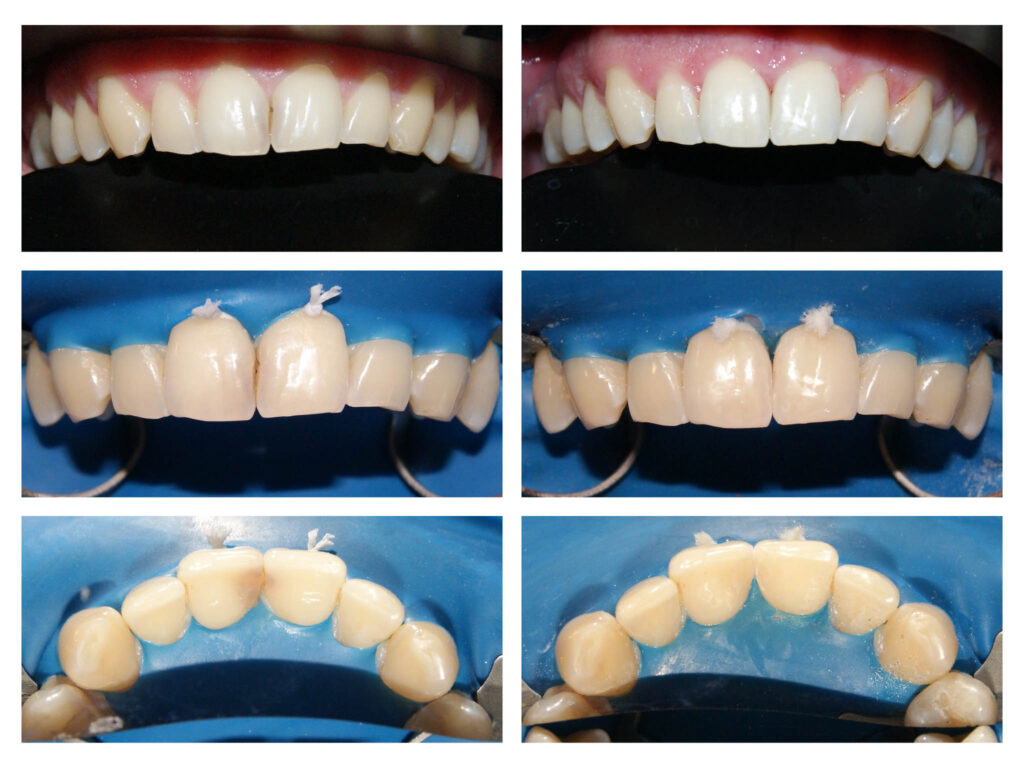

Zirconiu stratificat